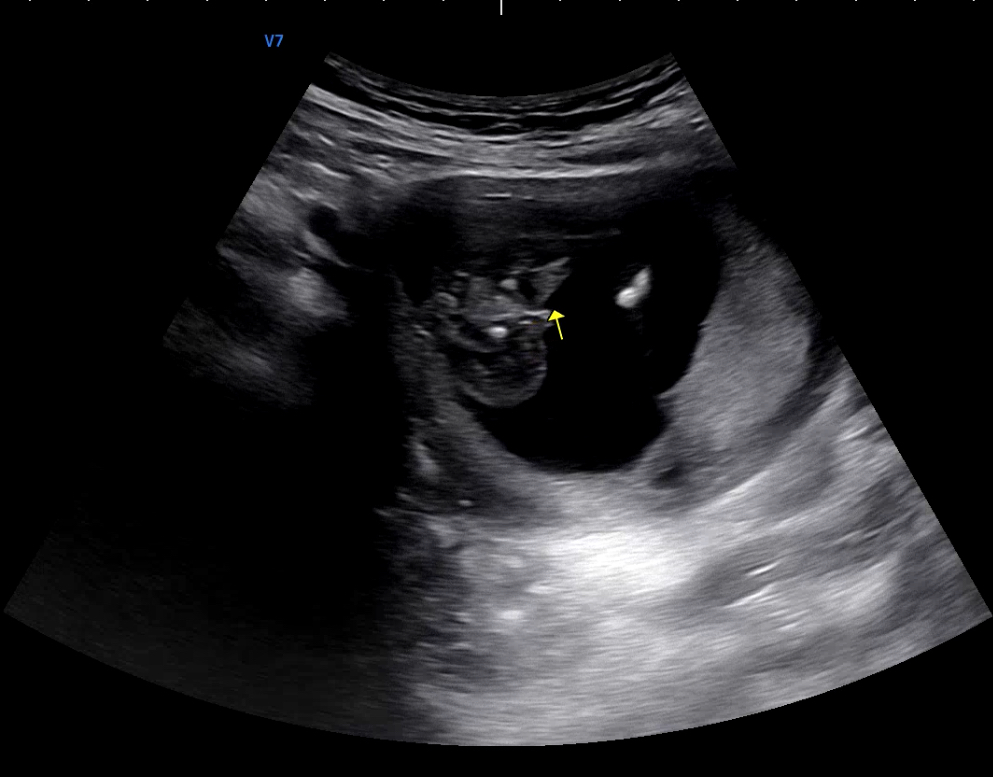

[20주 0일] 왕배의 성별을 알게 되었어요!

보통 16주만 돼도 성별을 알 수가 있다.특히 남아라면 대부분 16주면 알 수 있는 거 같다. 16주라도 아이의 성별을 모르는 경우는 아래와 같다.초음파 사진상 우람하게 다리 사이로 튀어나와 있는 게 잘 안 보인다아기가 다리를 꼬고 있다.탯줄인지 아니면 남아의 상징이 튀어나와있는 건지 애매하다왕배의 성별이 너무 궁금했으나 우리 부부도 16주 때는 알 수가 없었다.초음파 사진을 보면 뭐가 약간 튀어나와있는 거 같으면서도 아닌 거 같았고, 의사 선생님께 여쭤봐도 처음에는 남아인거 같았는데 자세히 보니깐 아닌거 같기도 하고 애매하다는 답변을 주셨다 🤷‍♂️🤷‍♂️오랑이: 저 사진대로라면 남자아이면 안돼. 너무 작아...  우리 부부는 51:49 정도의 의견으로 첫째는 딸이기를 임신 초반부터 원했었다. 나는..